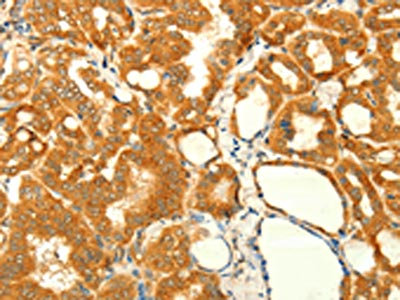

The image on the left is immunohistochemistry of paraffin-embedded Human colon cancer tissue using CSB-PA253076(NAPA Antibody) at dilution 1/35, on the right is treated with fusion protein. (Original magnification: ×200)

The image on the left is immunohistochemistry of paraffin-embedded Human thyroid cancer tissue using CSB-PA253076(NAPA Antibody) at dilution 1/35, on the right is treated with fusion protein. (Original magnification: ×200)